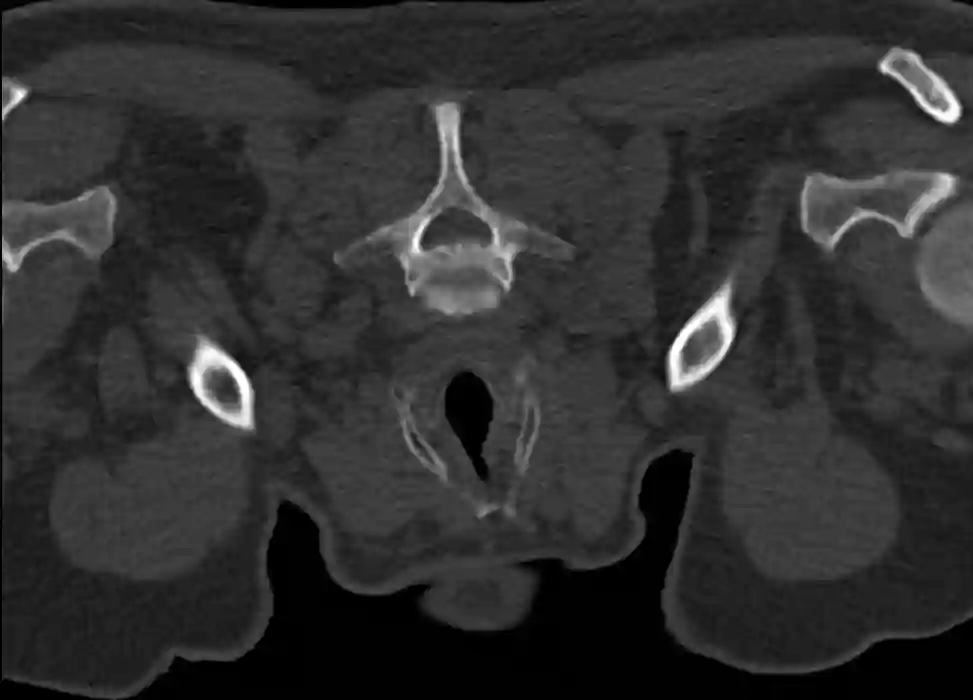

HWK 7 CT

Abbildung des siebten Halswirbelkörper im axialen CT Bild.